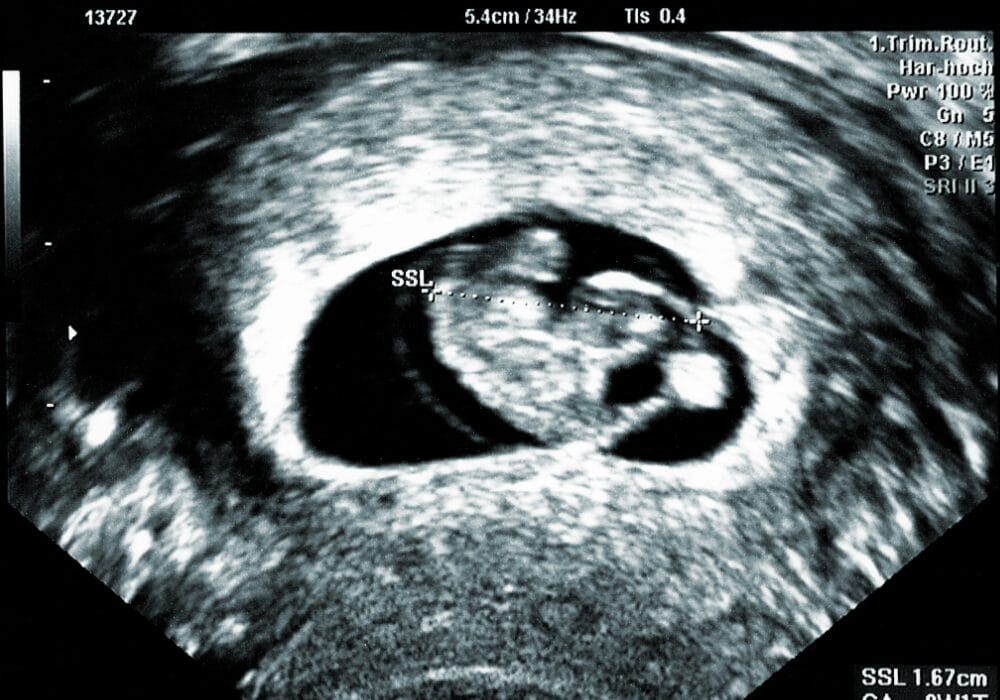

الأسبوع الخامس من الحمل يطلق على هذه الفترة بالفترة الجنينية حيث تبدأ أعضاء جسم الجنين بالتكون مثل القلب والجهاز العصبي والرئتين، ويمكن الشعور بنبض الجنين بداية من الأسبوع الخامس، ويمكن توضيح تطور نموه من خلال تكون الأديم الظاهر الخارجي الذي سيشكل الجهاز العصبي والأعضاء الخارجية مثل العينين والاذنين والعديد من الأنسجة، كما يتكون الأديم الداخلي وهو ما سيشكل الأعضاء الداخلية للإنسان، ويتكون الأديم الأوسط.

حجم طفلك في هذا الأسبوع يشبه إلي حد كبير حبة فلفل الأسود متناهي الصغر، ويتكون في داخله الكيس الصفار: وهو عبارة عن كيس مبطن بالغشاء يقوم بدوره بالتغذية خلال المراحل المبكرة الأولي لنمو الجنين داخل رحم الأم

يبلغ طوله : 0.05 in

يبلغ وزنه : 0.04 oz